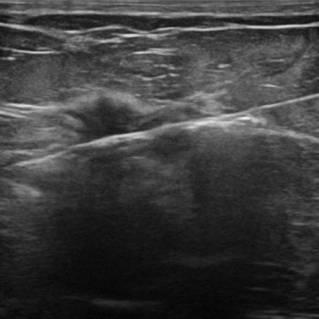

Ung thư vú

» Thông tin: Nữ giới – 56 tuổi.

» Lâm sàng: Khối tuyến vú.